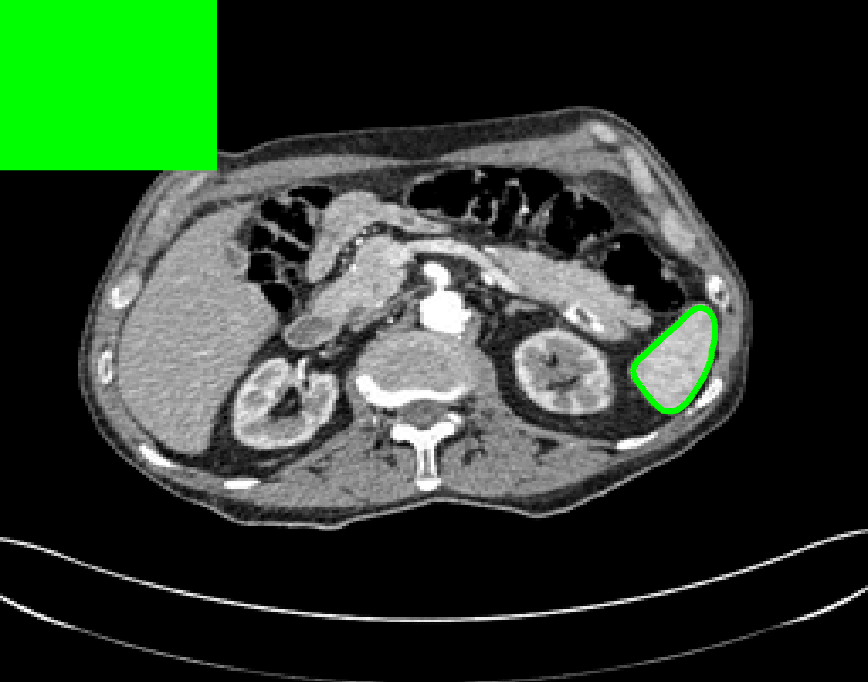

Test Images. We will perform initial tests on the images shown in Figs. 5–7. We have provided the ground truth and initialisation used for each image. Test Images 1–3 are synthetic, Test Image 4 is an MRI scan of a knee, Test Images 5–6 are abdominal CT scans, and Test Images 7–9 are lung CT scans. They have been selected to present challenges relevant to the discussion in §2. We focus on medical images as this is the application of most interest to our work. In the following we will discuss the results in terms of synthetic images (1–3) and real images (4–9). We also test the proposed approach on a larger data set of 30 CT images (a sample of which is presented in Fig. 18), comparing against existing selective methods detailed in §3.

Real Images. In Fig 12 we present results for Test Images 4–6. Here, the proposed model performs in a similar way to its competitors because these images are more typical selective segmentation problems in the sense that there is a clear distinction between the foreground and background intensities. In particular, the values in each case are: Test Image 4 , Test Image 5 , and Test Image 6 . It can be seen that the proposed model is competitive compared to previous approaches. The performance is quite poor for Test Image 5, but is arguably still the best for this challenging case. In Fig. 13 we present results for Test Images 7–9. Here the proposed model outperforms previous approaches significantly for each image. This is mainly due to the type of image considered. Specifically, the true intensities are: Test Image 7 , Test Image 8 , and Test Image 9 . The proposed model is capable of achieving results where , with other models failing completely in these cases.